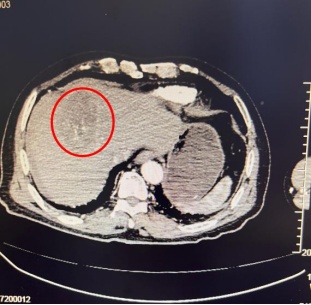

急诊科紧急行CT检查显示,李奶奶肝左叶有一直径约96mm*68mm的巨大肿瘤,且已发生破裂出血,肝周可见明显积液。结合患者病史,明确诊断为“肝恶性肿瘤破裂出血”。肿瘤微创介入诊疗中心王小军主任表示,肝癌破裂是原发性肝癌严重并发症,发病急、进展快,若不及时救治,短时间内就可能因失血性休克危及生命。

术前CT示:肿瘤破裂出血